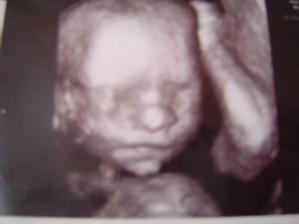

Nas druhy pokladik

29. 12. 2008 sme zistili ze snad budeme druhy krat rodicia z coho sa veeeelmi tesime. Brusko pekne rastie a uz sa tesime na male babatko 🙂

24. 8. 2009 sa nam narodil maly Jakubko s mierami 54cm a 3850g. Je to nasa druha laska a lubime ho velmi prevelmi 🙂